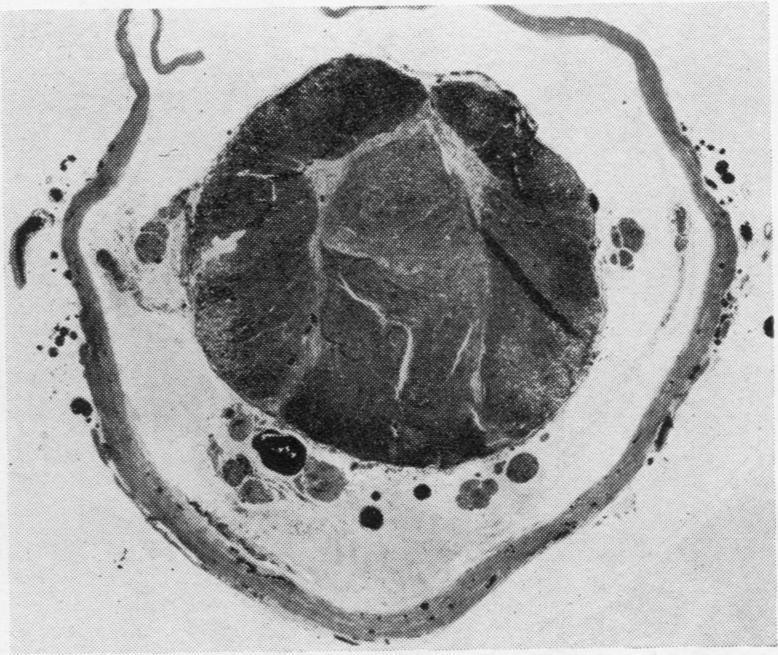

The clinical and pathological findings are described of a fatal case of acute haemorrhagic leucoencephalitis and disseminated encephalomyelitis with acute necrosis of the white matter of the spinal cord. It is suggested that the reaction was a severe immunological response of an allergic nature, probably due to antitetanus serum.